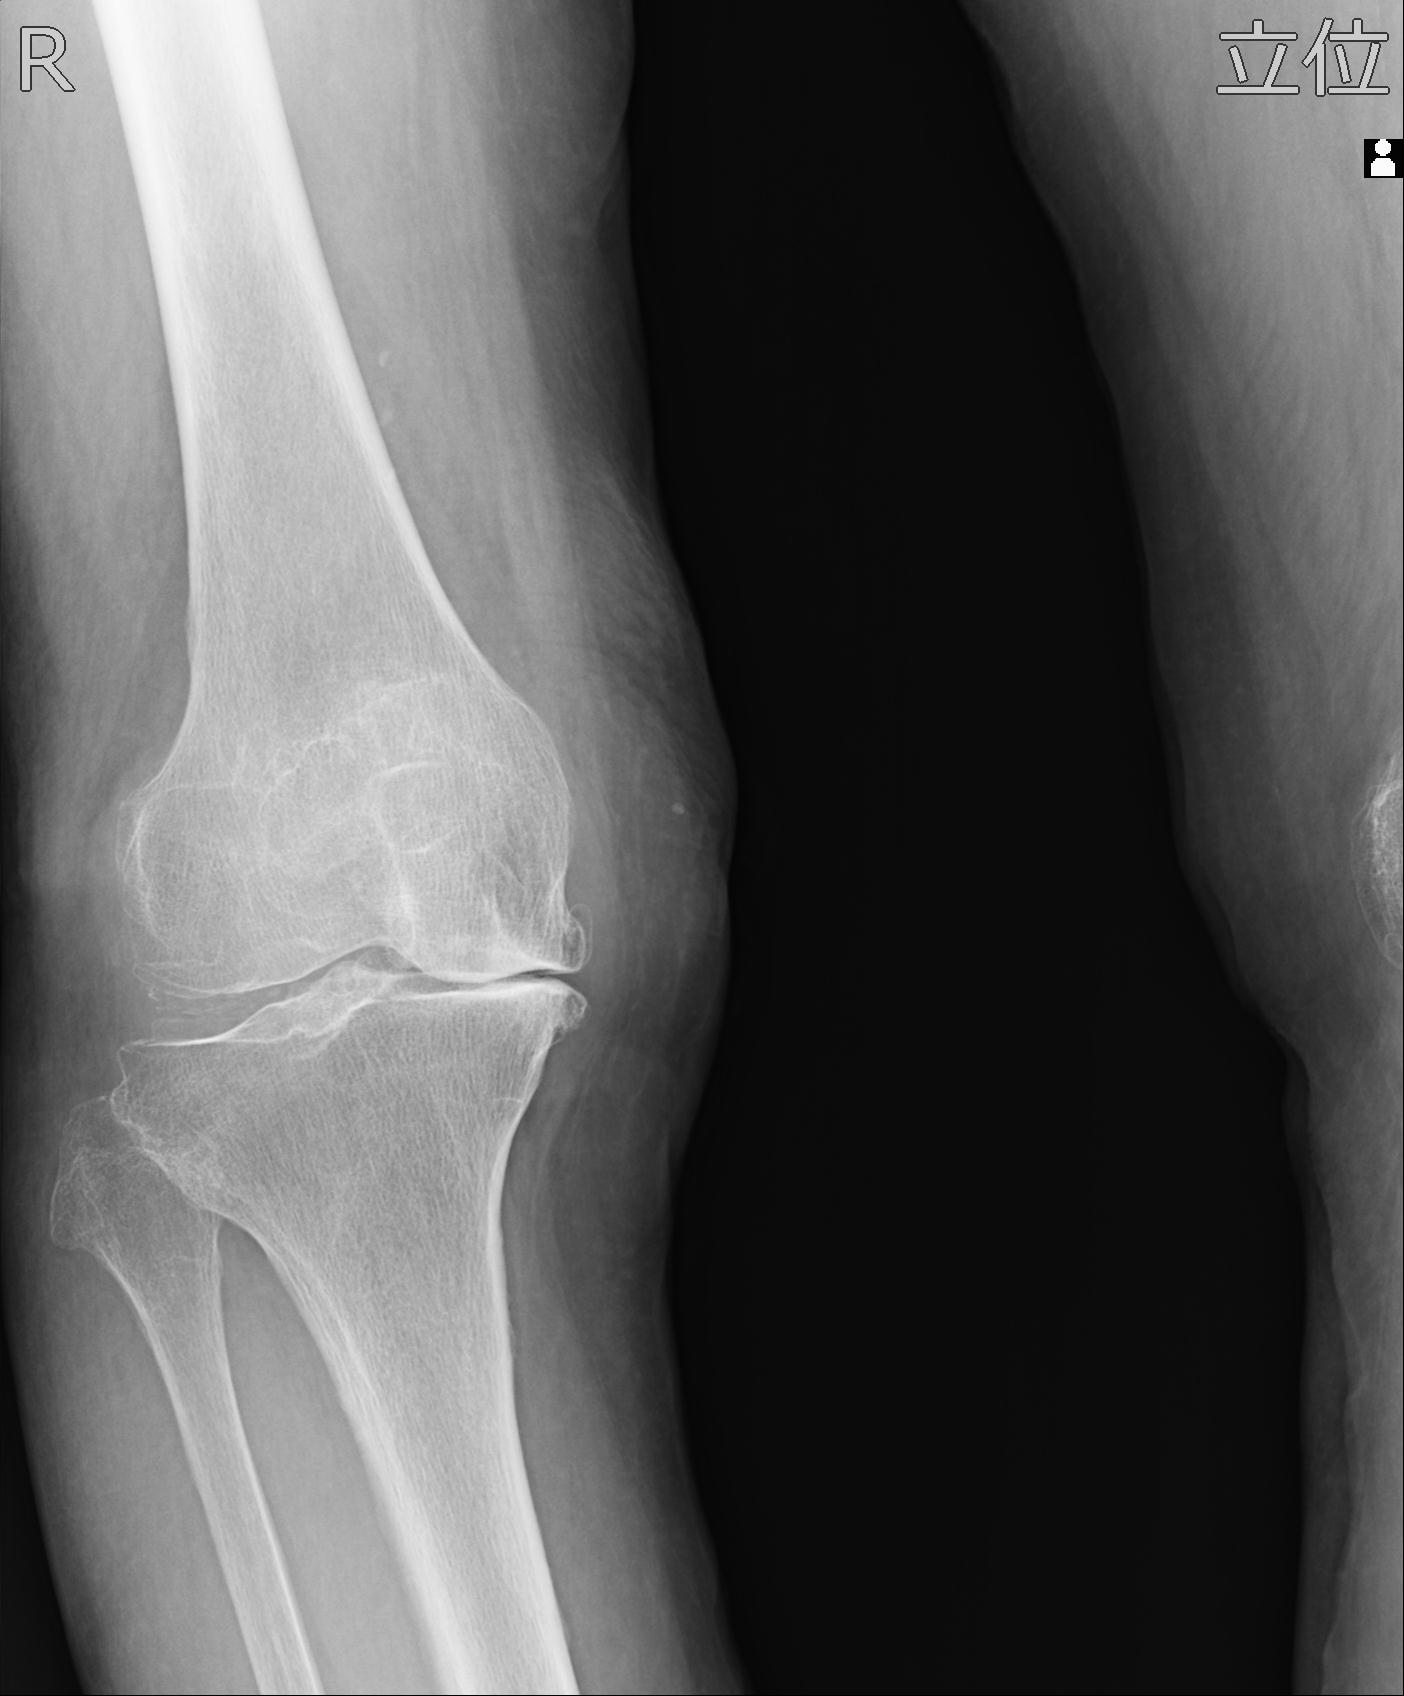

100612 11/25 1/20 右膝 2R 84歳女性 右TKA